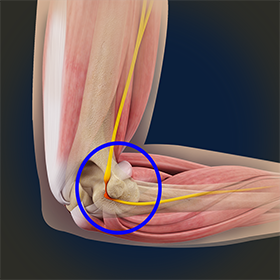

When the elbow is bent, the ulnar nerve can stretch and catch on the bony bump. When the ulnar nerve is compressed or entrapped, the nerve can tear and become inflamed, leading to cubital tunnel syndrome. The ulnar nerve travels down the back of the elbow behind a bony bump called the medial epicondyle, and through a passageway called the cubital tunnel.

When the elbow is bent, the ulnar nerve can stretch and catch on the bony bump. When the ulnar nerve is compressed or entrapped, the nerve can tear and become inflamed, leading to cubital tunnel syndrome. In general, the signs and symptoms of cubital tunnel syndrome arise gradually, progressing to the point where you have to seek medical attention.